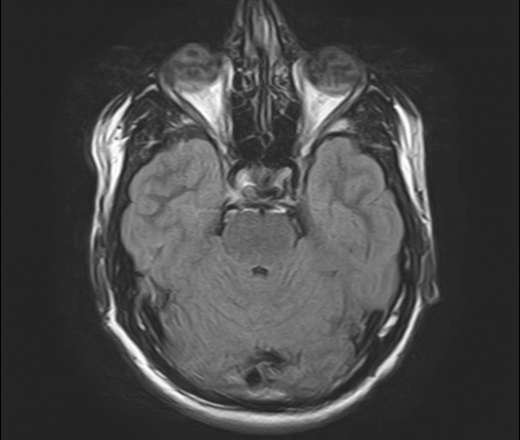

Что такое эктопия миндалин мозжечка Эктопия миндалин мозжечка считается специфическим опущением мозжечкового миндалевидного тела в крупное отверстие области затылка . Зачастую аномалию именуют мальформацией Арнольда Киари, возникающей по причине каудальной дислокации миндалевидного тела левой либо правой части головного мозга .

Больше всего волнует эктопия правой миндалины мозжечка . Правая миндалина мозжечка расположена ниже уровня нижнего края большого затылочного отверстия на 2 мм .